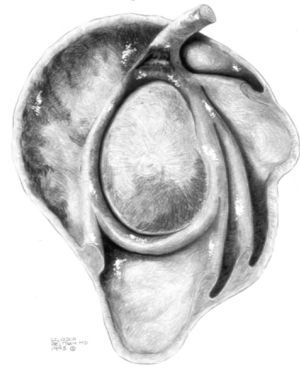

ALPSA (anterior labroliamentous periosteal avulsion)

Al igual que en el apartado anterior, existe también una separación de LG junto con la cápsula y el periostio, pero a diferencia de las lesiones de Bankart o Perthes, el LG se desplaza hacia dentro, por detrás del borde de la glenoides18 (fig. 12). La lesión de ALPSA puede cicatrizar por sinovialización (fig. 12), pero continúa siendo de carácter inestable.

Fig. 12.--ALPSA (anterior labroliamentous periosteal avulsion) agudo (A) y crónico (B). Nótese la separación del labio glenoideo y su desplazamiento posterior y medial por detrás del reborde glenoideo (flecha en A). En una fase crónica el labio glenoideo no se distingue como una estructura separada, sino como un engrosamiento de la unión entre el labio, la cápsula y el periostio (flecha en B).